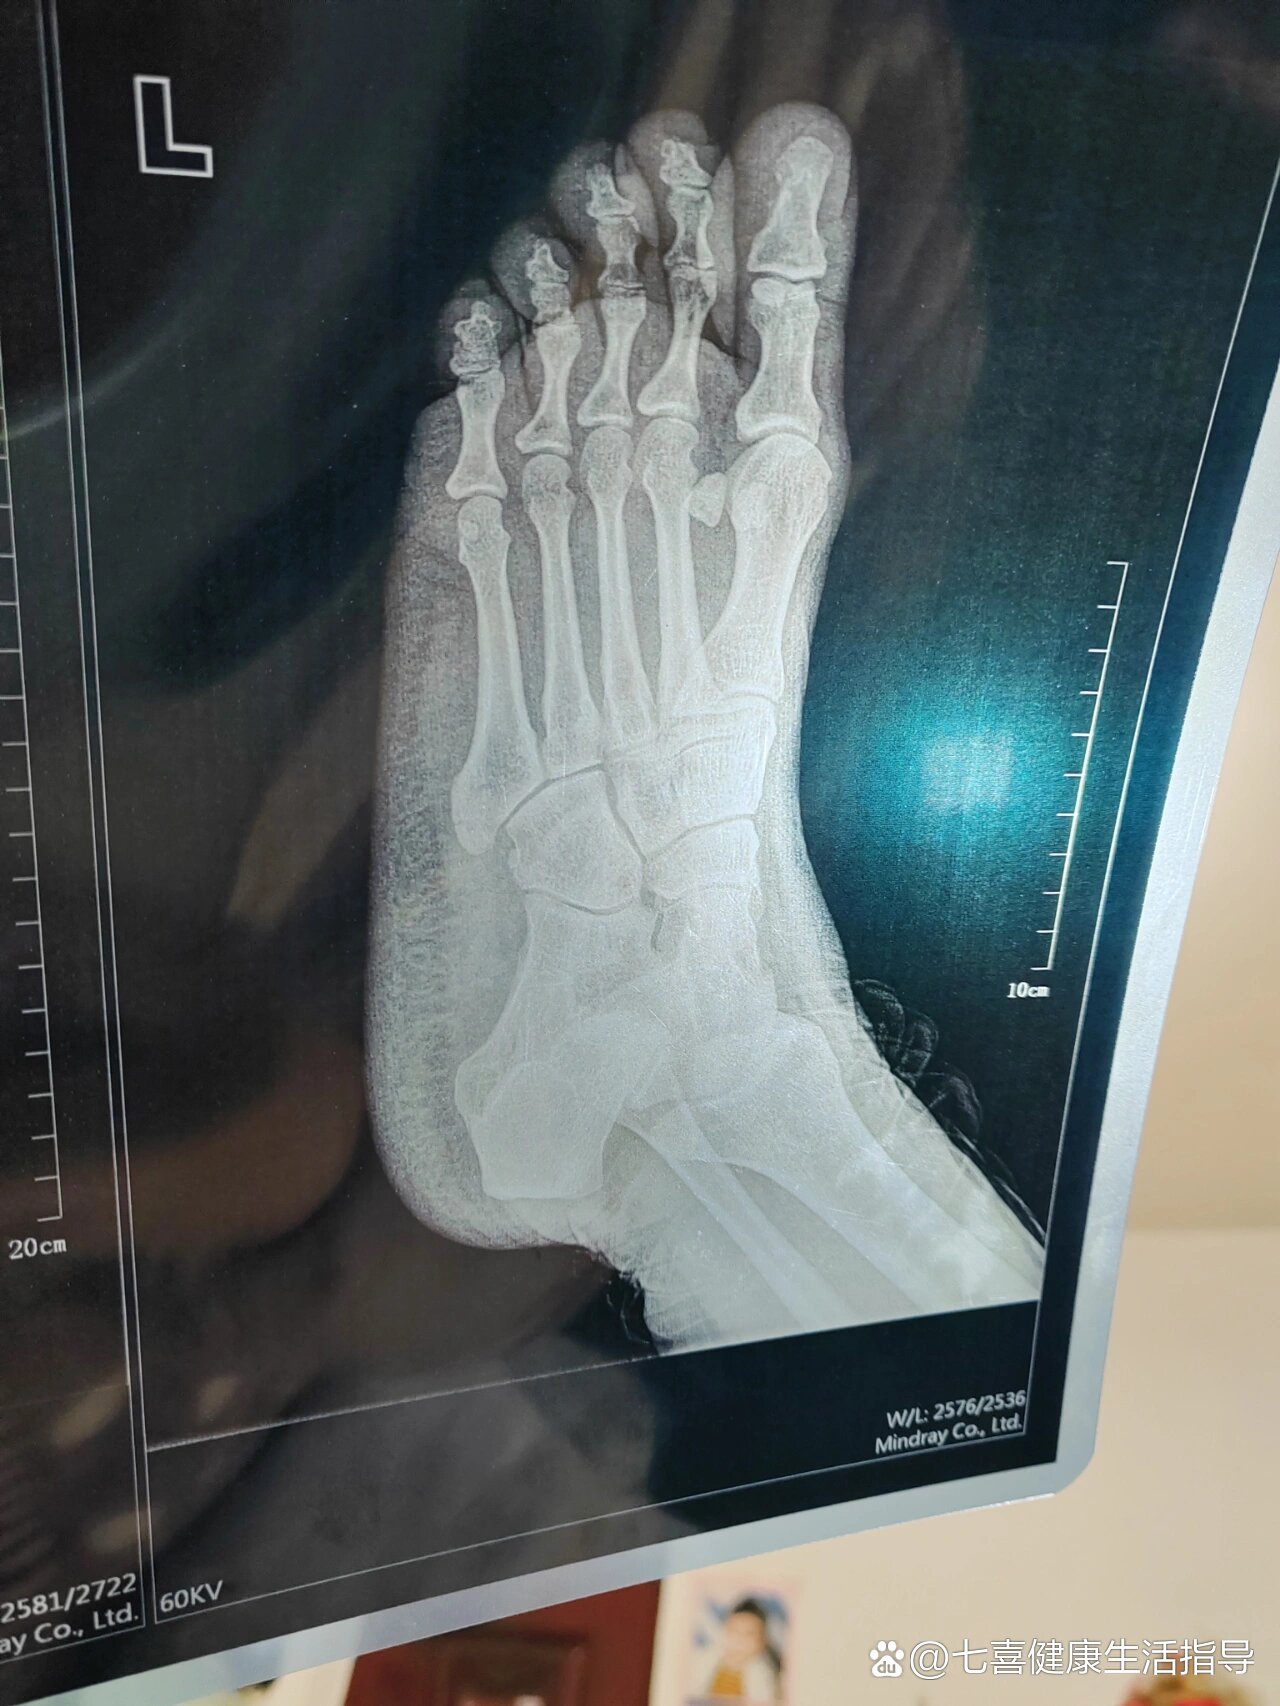

左脚第5跖骨基底部骨折,慢慢康复路

木与子 的想法: 记录左脚骨折全过程